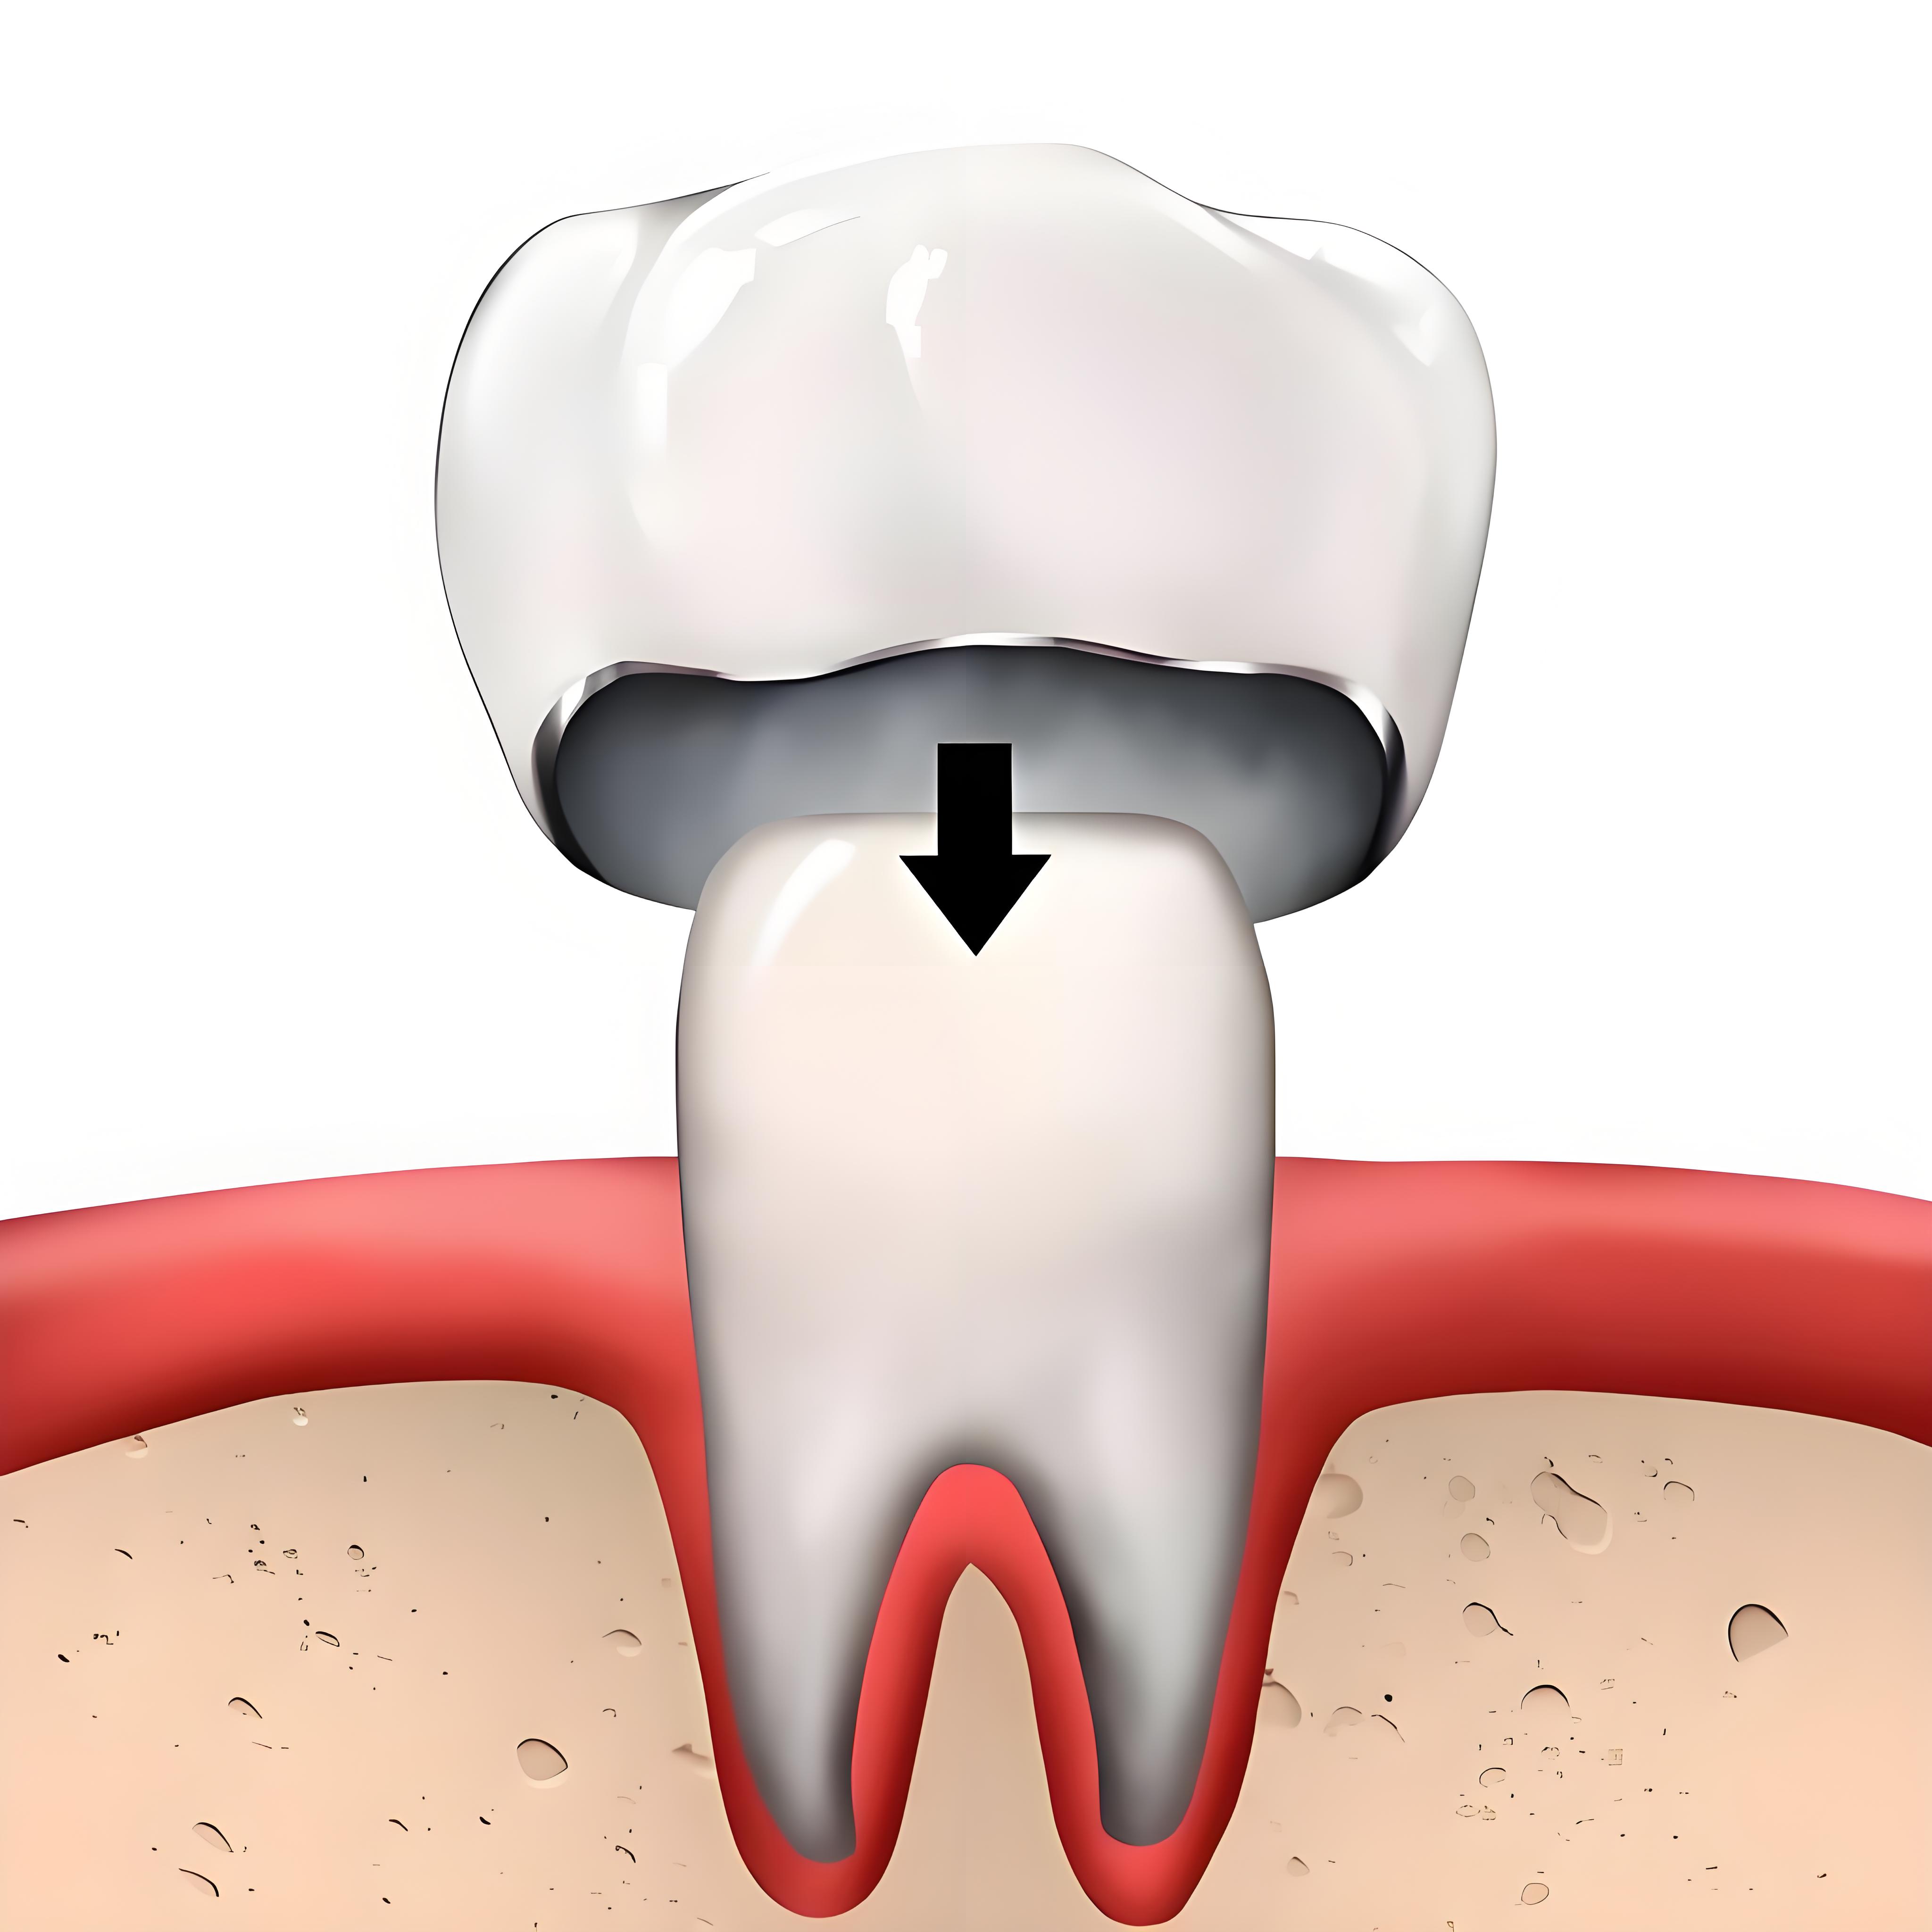

在深圳,做牙套的收費是根據牙套的材料以及品牌所決定,醫生的經驗也會影響最終牙套的收費。常見的磨牙牙套分為兩種,一種是全瓷牙套、一種是烤瓷牙套。全瓷牙套一般有愛爾創全瓷牙套、威蘭德全瓷牙套、德國澤康全瓷牙套、lava全瓷牙套。收費分別是愛爾創全瓷牙套收費是1500左右、德國威蘭德全瓷牙套是2500左右,德國澤康全瓷牙套是4000左右、美國lava全瓷牙套5000左右。

烤瓷牙套的收費是一般是1000左右,當然如果含有貴重金屬,比如黃金等,價格會在1000基礎上+貴重金屬成本費。

做牙套涉及到磨牙,磨牙是做牙套過程的常見步驟,磨牙磨多少以及磨牙是否使得牙冠貼合都是十分重要的一件事情,主要是由醫生的經驗所決定的,因此尋找靠譜的牙科做牙套是十分重要的,深圳做磨牙牙套哪家牙科比較專業呢?

維港口腔,香港企業領袖品牌,口岸開設十七年,在福田口岸、羅湖口岸廣設門店。維港口腔擅長做牙套嘅醫生有數十位,比如碩士牙醫孫睿、三十年經驗牙醫陳曉醫生、廣東話牙醫賴成文醫生等,她們經驗豐富,能夠借高清三維立體CT成像,數字化分析牙齒的情況,然後根據牙齒的情況進行綜合的磨牙,磨牙量少磨牙精確度高。維港口腔做磨牙牙套的收費相對比較便宜。維港口腔磨牙牙套的質保期長達三到五年,質保時間是遠遠高於行業的普通週期的。因此,維港口腔無論在醫生的技術、醫療設備、質保、收費還是穩定經營方面都是值得選擇的牙科。